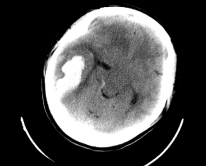

王峰医生描述,女患者长相清秀,身高 1 米 6,身材不是很胖,年纪也很轻,照理来说不是中风的高危人群。当时,一系列检查之后诊断明确,颅内出血 30ml 左右,情况紧急,由神经外科立即为她做了开颅手术,清除血肿。

患者右侧顶枕叶脑出血